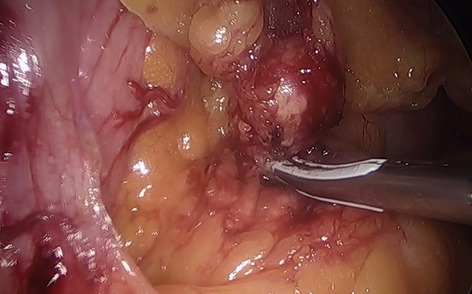

Until now there have been early attempts at producing advanced laparoscopic systems but these have been cumbersome and limited in their engineering. We present a revolutionary new advanced laparoscopic instrumentation system called ArtiSential. The ArtiSential instruments include bipolar forceps, Maryland dissector, monopolar spatula, monopolar hook, needle holder, with more on the way. They allow a wide range of articulating movement through 7 degrees of freedom that can mimic the dexterity of robotic platforms (Fig. 1). Traditional laparoscopic instruments have limited range of movements but these instruments allow for complex articulating movements in different planes which can be further exploited around the fulcrum of the port. This additional articulation means that there is better access to difficult part of anatomy. Furthermore, there is tactile feedback on the instrument handset which is lightweight and disposable.

Our initial series of cases include pelvic colorectal surgery and demonstrate the advantages of articulating instruments (Fig. 2). Further, we demonstrate that there is a learning curve to these instruments to maximise their benefit during complex procedures. We suggest adopting the formal training programme which includes a period of dry lab training before embarking on clinical cases so that surgeons may truly benefit from these advanced instruments. This also allows for safer introduction of new technology.